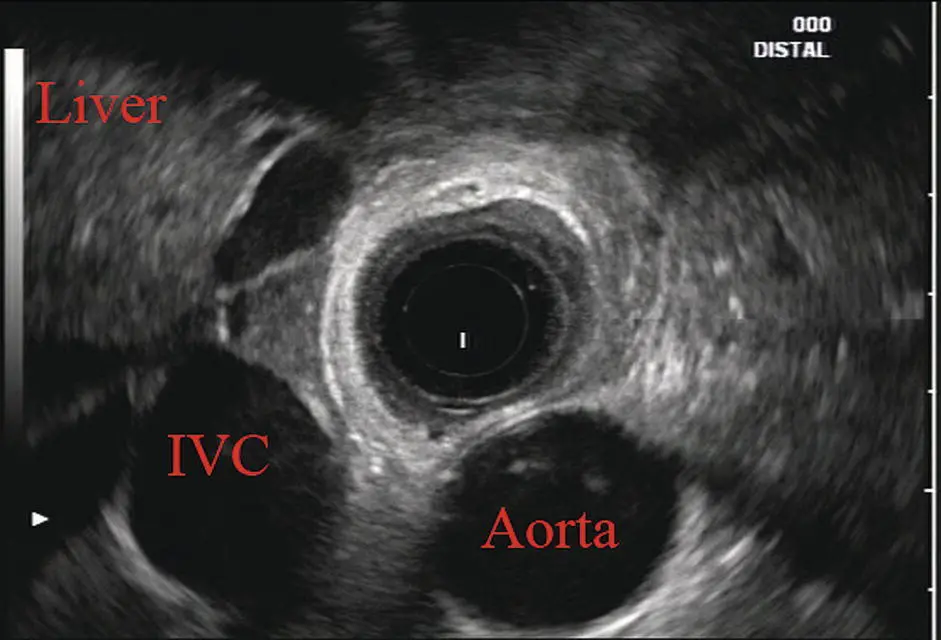

Further withdrawal upward to usually around 30–35 cm reveals the anechoic chamber of the left atrium in the 12 o’clock position ( Figure 2.3). With this field, relatively slight movement of the scope will reveal the mitral valve ( Figure 2.4), aortic root, and the aortic valve ( Figure 2.5). In the inferior portion of the field the descending aorta, the spine, the thoracic duct, and a relatively prominent azygos vein can be seen.

Figure 2.3 Radial array image at the level of the left atrium. PV, pulmonary vein.